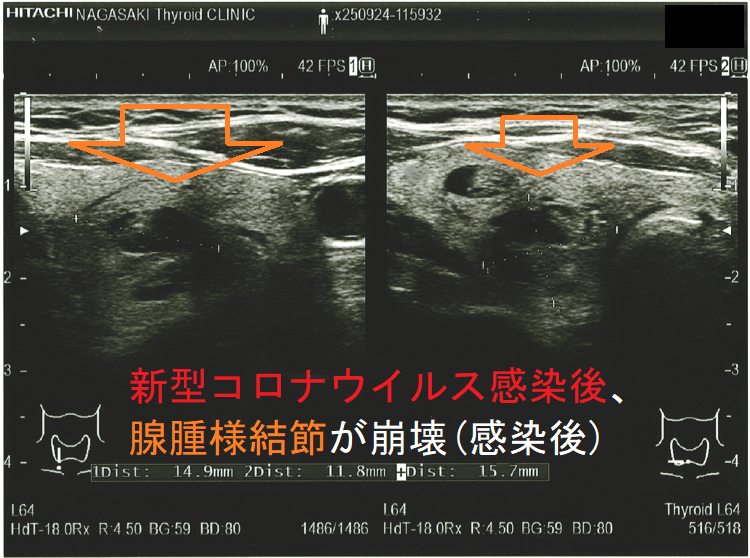

新型コロナウイルス感染(COVID-19)後、腺腫様結節が崩壊(感染後);感染後、内部は崩壊し、亀裂部に液体が充満。のう胞型腺腫様結節(嚢胞型腺腫様結節)のようになってしまった。